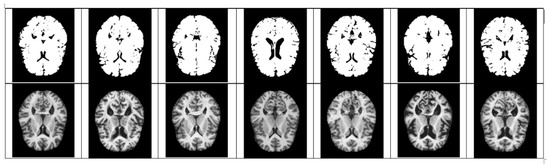

- As mentioned above, the method of diagnosing AD on MRI images compares the size of the hippocampus. However, due to the nature of the existing CNN model, it is difficult to detect because it is not sensitive to image dispersion. Therefore, additional processing of the color space of the image is required.

- For Z-score normalization, the interval to which each pixel belongs is converted to [−1, 1], and for min–max, it is converted to [0, 1]. During the computation of the convolutional neural network, the pixel intensity of [0, 255] is adjusted for fast convergence and accurate feature extraction.

- The size space of pixels constituting the Alzheimer’s MRI data set is [0, 255]. Among them, patients with AD with reduced hippocampus will have more pixels close to zero than normal people. On the premise of this, the average value of pixel intensities in each MRI image is set as a threshold value. Alzheimer’s should recognize changes in size contraction rather than changes in brain function. Based on this information, it is necessary to set the space as an important feature for the color information of MRI rather than a feature representing the shape of the brain.